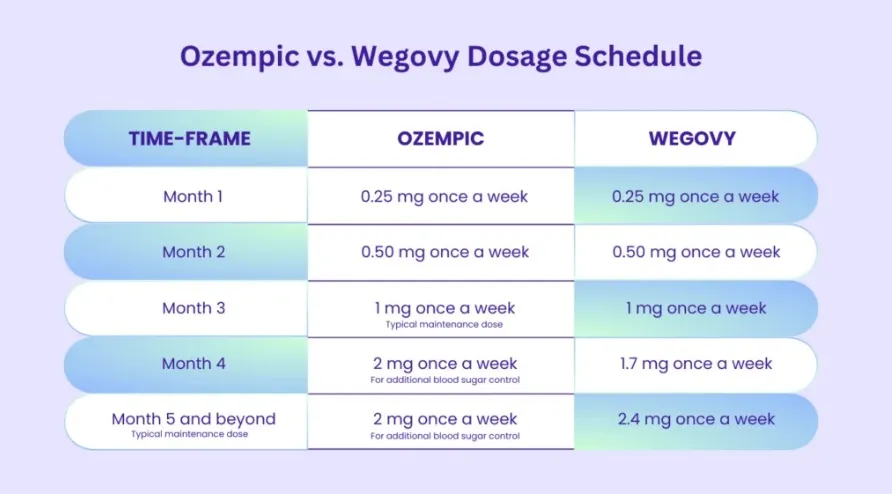

Para otimizar os resultados e minimizar os efeitos adversos, uma titulação gradual é essencial. Uma proposta prática inclui:

* Início: Iniciar com 0,25 mg administrados semanalmente durante as primeiras 4 semanas, permitindo a adaptação do paciente e reduzindo o risco de eventos adversos, principalmente gastrointestinais.

* Primeiro Ajuste: Aumentar para 0,5 mg semanais após o período inicial, mantendo essa dose por, pelo menos, mais 4 semanas para avaliação da tolerabilidade e resposta clínica.

* Escalada Progressiva: Em pacientes que demonstram boa tolerância, proceder com aumentos graduais para 1,0 mg, depois 1,7 mg e, finalmente, atingir 2,4 mg semanais – a dose considerada ideal para maximizar os efeitos na perda de peso.

Se o paciente já estiver fazendo uso do Ozempic (sem conflito de interesse), podemos fazer a transição para o Wegovy (sem conflito de interesse) conforme a tabela abaixo.